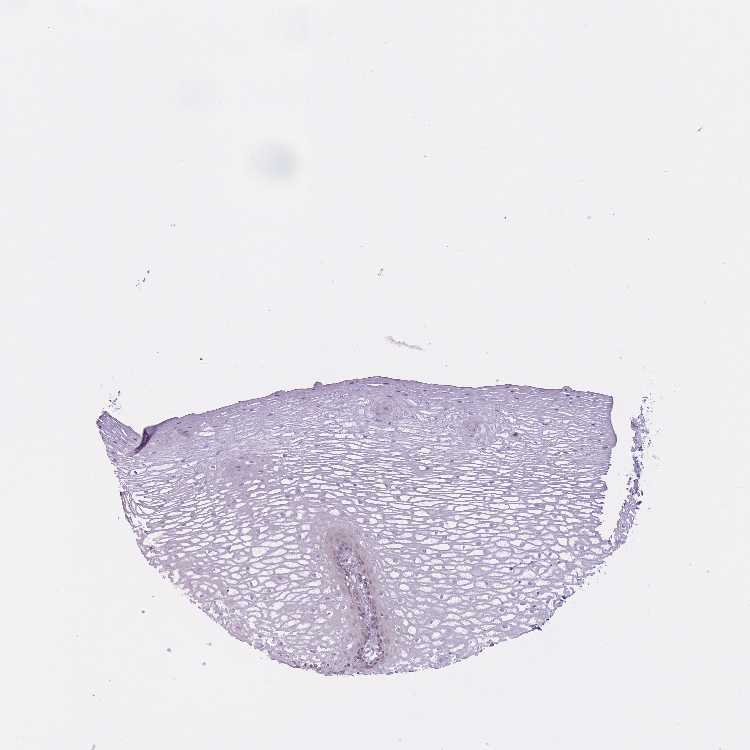

ESOPHAGUS - Antibody stainingi

Antibody staining in the annotated cell types in the current human tissue is reported as not detected, low, medium, or high, based on conventional immunohistochemistry profiling in selected tissues. This score is based on the combination of the staining intensity and fraction of stained cells.

Each image is clickable and will lead to virtual microscopy that enables deeper exploration of all samples and also displays staining intensity scores, fraction scores and subcellular localization as well as patient and tissue information for each sample.

Antibody HPA048149

Squamous epithelial cells Low